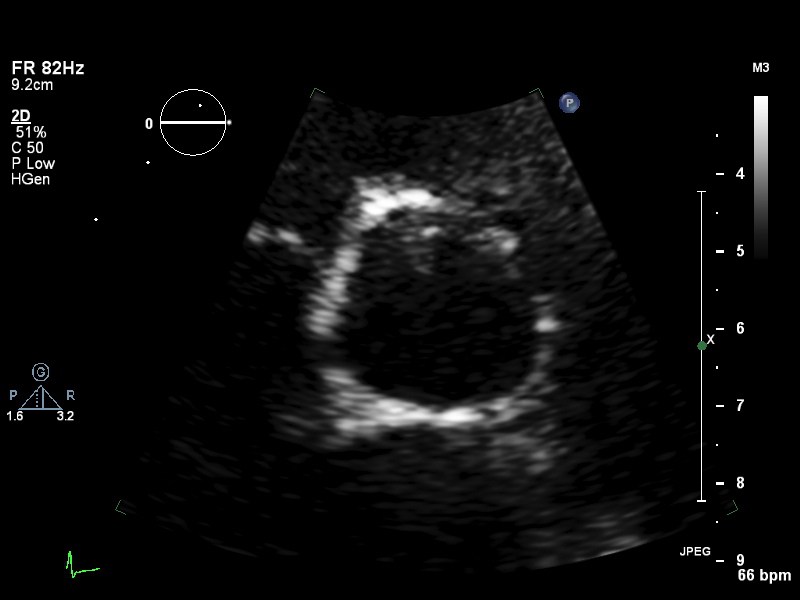

ImageView NameDescription

psax-av psax-av Focused on aortic valve